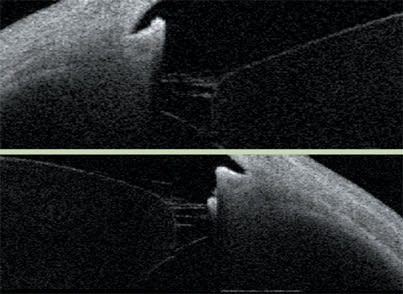

A narrow angle is apparent with Visante OCT imaging, in this case 9.5°.

An anterior-segment scan shows a patent peripheral iridectomy but also plateau iris syndrome.

This image shows peripheral anterior synechiae on gonioscopy and the Visante OCT.

Imaging illustrates a very narrow angle and the need for a lensectomy. The lensectomy accomplished the goal of a much more open anatomy.